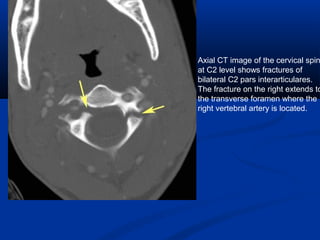

Hangman's Fracture- # through pars of c2

Axial CT image of the cervical spin

at C2 level shows fractures of

bilateral C2 pars interarticulares.

The fracture on the right extends to

the transverse foramen where the

right vertebral artery is located.